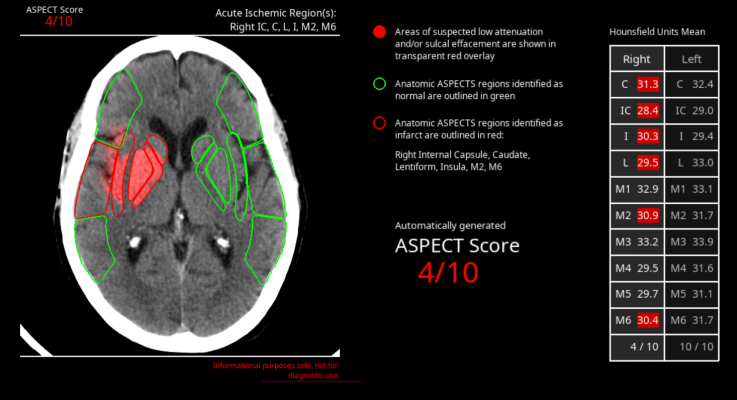

- CINA-ASPECTS is a quantification tool that automatically measures an ASPECT Score to assess ischemic changes in stroke. CINA-ASPECTS enables faster, more consistent, and more precise interpretations for assessing acute ischemic stroke.